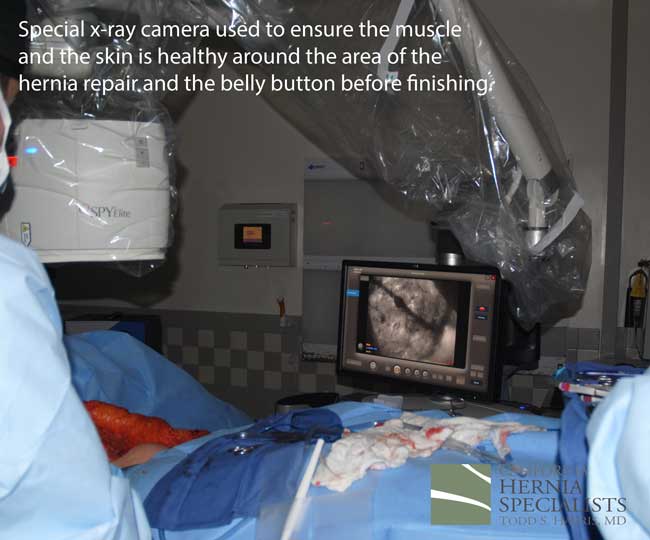

This technique requires more surgical time, recovery time, and usually several days in the hospital. However, this patient chose to proceed with the open hernia repair. Below are some of the pictures from his surgery as well as post operative CT scan image and photos of the patient.